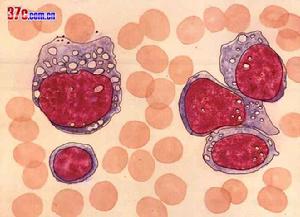

白血病急性白血病(AcuteLeukemia)以粒細胞型和淋巴細胞型多見,前者多發於成年,後者多發於兒童,單核細胞型少見。尤以兒童和青年為多,50歲以上起病者常類似慢性白血病。白血病患者的主要表現症狀有以下幾個方面: